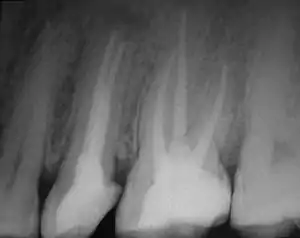

Планирование, а также решение поставленных задач формирования, очистки и обтурации корневых каналов в ходе эндодонтического лечения чреваты реальными и потенциальными опасностями, связанными со сложностью анатомического строения системы корневых каналов, а также техническими особенностями их инструментальной обработки, дезинфекции и пломбирования. В процессе эндодонтического лечения и после заполнения корневых каналов зуба могут возникать проблемы:

- ятрогенные ошибки (например, перфорация корня[8][9]);

Воспалительный процесс будет неизменно и планомерно разрушать слои зуба, провоцируя нестерпимую боль и неприятные последствия, главным из которых может стать потеря зуба. Кроме того, в некоторых случаях может потребоваться резекция корня или перепломбировка корневых каналов зуба. При этом основной задачей стоматолога является максимально полное заполнение канала корня пломбировочным материалом, предотвращающим возможное появление воспаления в дальнейшем. С этой целью широко применяются определённые пломбировочные составы, в состав которых добавлены антисептики. Для достижения поставленной цели в современных реалиях зачастую практикуются механические, а также медикаментозные методы. Механическая обработка корневых каналов может осуществляться при помощи соответствующих инструментов и современного оборудования, вплоть до эндодонтических моторов и так далее. В процессе медикаментозной распломбировки корневых каналов используют препараты, изготовленные на основе органических растворителей, которые способны изменять структуру пломбы. Альтернативным способом распломбировки каналов, заполненных цементом является использование специальных ультразвуковых эндонасадок, с помощью которых пломба удаляется за одно посещение стоматолога. Этот метод широко применяется в случаях, когда анкерный штифт не был установлен одномоментно с обтурацией корневого канала для распломбировки ранее вылеченного зуба под анкерный штифт для последующей реставрации коронки. Выполнение такой операции требует особой аккуратности, поскольку для последующей установки штифта необходимо сохранить часть пломбы, которая должна герметично закрывать верхушку корневого канала[10].